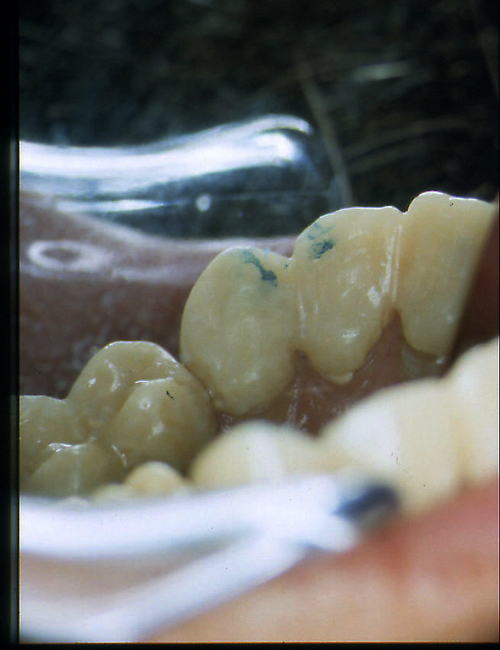

ABSTRACT El Bruxismo es una entidad patológica en la que concurren diferentes factores. Entre ellos el stress que conlleva consigo la vida moderna, constituye el Factor Predisponente sobre el que se ha abundado en innumerables tratamientos de tipo general, actuando sobre la psiquis y el comportamiento del individuo, ya sea con fármacos o bien mediante medios psicológicos. Sin embargo, como tantos desequilibrios provocados por el stress, confluyen siempre con un Factor Desencadenante, que en el caso del Bruxismo se encuentra en las desarmonías entre los componentes varios del Sistema Estomatognático. DESARROLLO Paciente varón, de 43 años, constitución atlética. A la inspección se observan desgastes oclusales que alcanzan la calidad de Facetas Parafuncionales, con dentina expuesta y empastes totalmente gastados y evidentes signos de falta de Disclusión Canina de ambos lados. Sobre dicho montaje se realiza un Encerado Progresivo de Diagnóstico, aportando en el mismo los elementos necesarios para obtener todos los principios básicos de una Oclusión Orgánica. FIG. 6 a 24 Una vez aprobado el fisiologismo de la oclusión en el articulador, se reproducen modelos de yeso con la nueva situación, y se estampa un SET UP en cada maxilar. FIG. 25/26 Procedemos entonces al tallado de las piezas correspondientes a la Guía Anterior, y rebasamos los estampados, creando en boca una nueva situación desoclusiva, que permanece en boca durante los pocos días que transcurren entre la primera y segunda visita de trabajo. FIG. 27/33 Ya abordando en esta segunda visita los sectores posteriores, tanto superiores como inferiores, tallamos siempre de manera supragingival, destacando la importancia vital de la forma obtenida en las provisionales, a las que abrimos plenamente las troneras para lograr una correcta higiene. FIG.34 a 43 FIG. 44 a 52 Efectuados los colados en oro y probados en boca, en el laboratorio se confecciona el bizcochado de la nueva Guía Anterior, la que puede o no copiarse de la Guía Anterior provisional, mediante la técnica denominada Trayectoria Funcionalmente Generada, que consiste en realizar en la platina del articulador un registro estereográfico sobre acrílico Duralay en polimerización. FIG. 57/58 Ajustados todos los detalles mediante esta técnica, se instala en boca en forma Provisional y se deja funcionando una semana o dos, al cabo de las cuales se chequean las disclusiones , los ajustes, la eficacia masticatoria, la carencia de sintomatología articular y muscular. FIG.59 a 63 PIE DE FOTO FIG.9 OBTENCIÓN DE LA GUÍA ANTERIOR FIG.10 Y 11 PITOMBOS. ALINEAC. TRIDIMENSIONAL FIG.12 PITOMBOS. DISCLUSIÓN DER. FIG.13 PITOMBOS. DISCLUSIÓN IZQ. FIG.14 WILSON INF. FIG.15 WILSON SUP. FIG.16 BOCA DE PEZ INF. FIG.17 BOCA DE PEZ SUP. FIG.18 VISTA OCLUSAL FIG.19 O.R.C. FIG.20 DISCLUSIÓN DERECHA FIG.21 CRESTAS TRIANG. INT. FIG.22 CRESTAS TRIANG. INT. FIG.23 CRESTAS TRIANG. INT. FIG 24 CRESTAS TRIANG. INT. FIG.59 DISCLUSIÓN IZQ. FIG.60 DISCLUSION IZQ. FIG.61 DISCLUSIÓN DER. FIG.62 DISCLUSION DER. FIG. 63 AJUSTE PERIFÉRICO